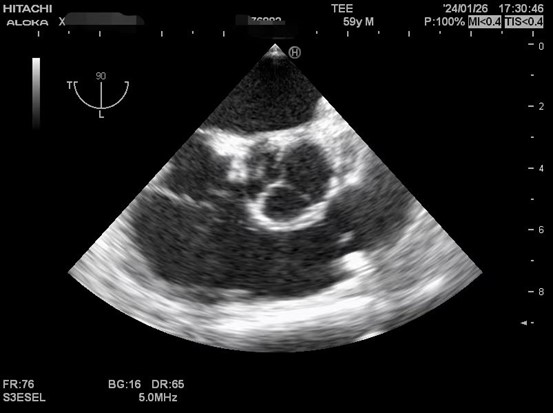

肝硬化患者术前合并症较多,术中血流动力学波动剧烈,围术期可能发生严重低血压、心内血栓形成、肺栓塞、左室流出道梗阻、心室收缩舒张功能不全等危急事件,给麻醉管理带来巨大挑战。TEE是将超声探头放在食管中段或胃底,从心脏后方持续观察心脏结构和功能,避免肺气对成像的影响,图像清晰且不影响手术的操作,是肝移植术中重要的监测手段之一。美国心脏超声协会及美国心血管麻醉医师学会均推荐肝移植术中常规使用TEE。目前美国各大移植中心术中麻醉科术中常规使用TEE进行持续监测。

以下是肝移植术中TEE监测的图像。